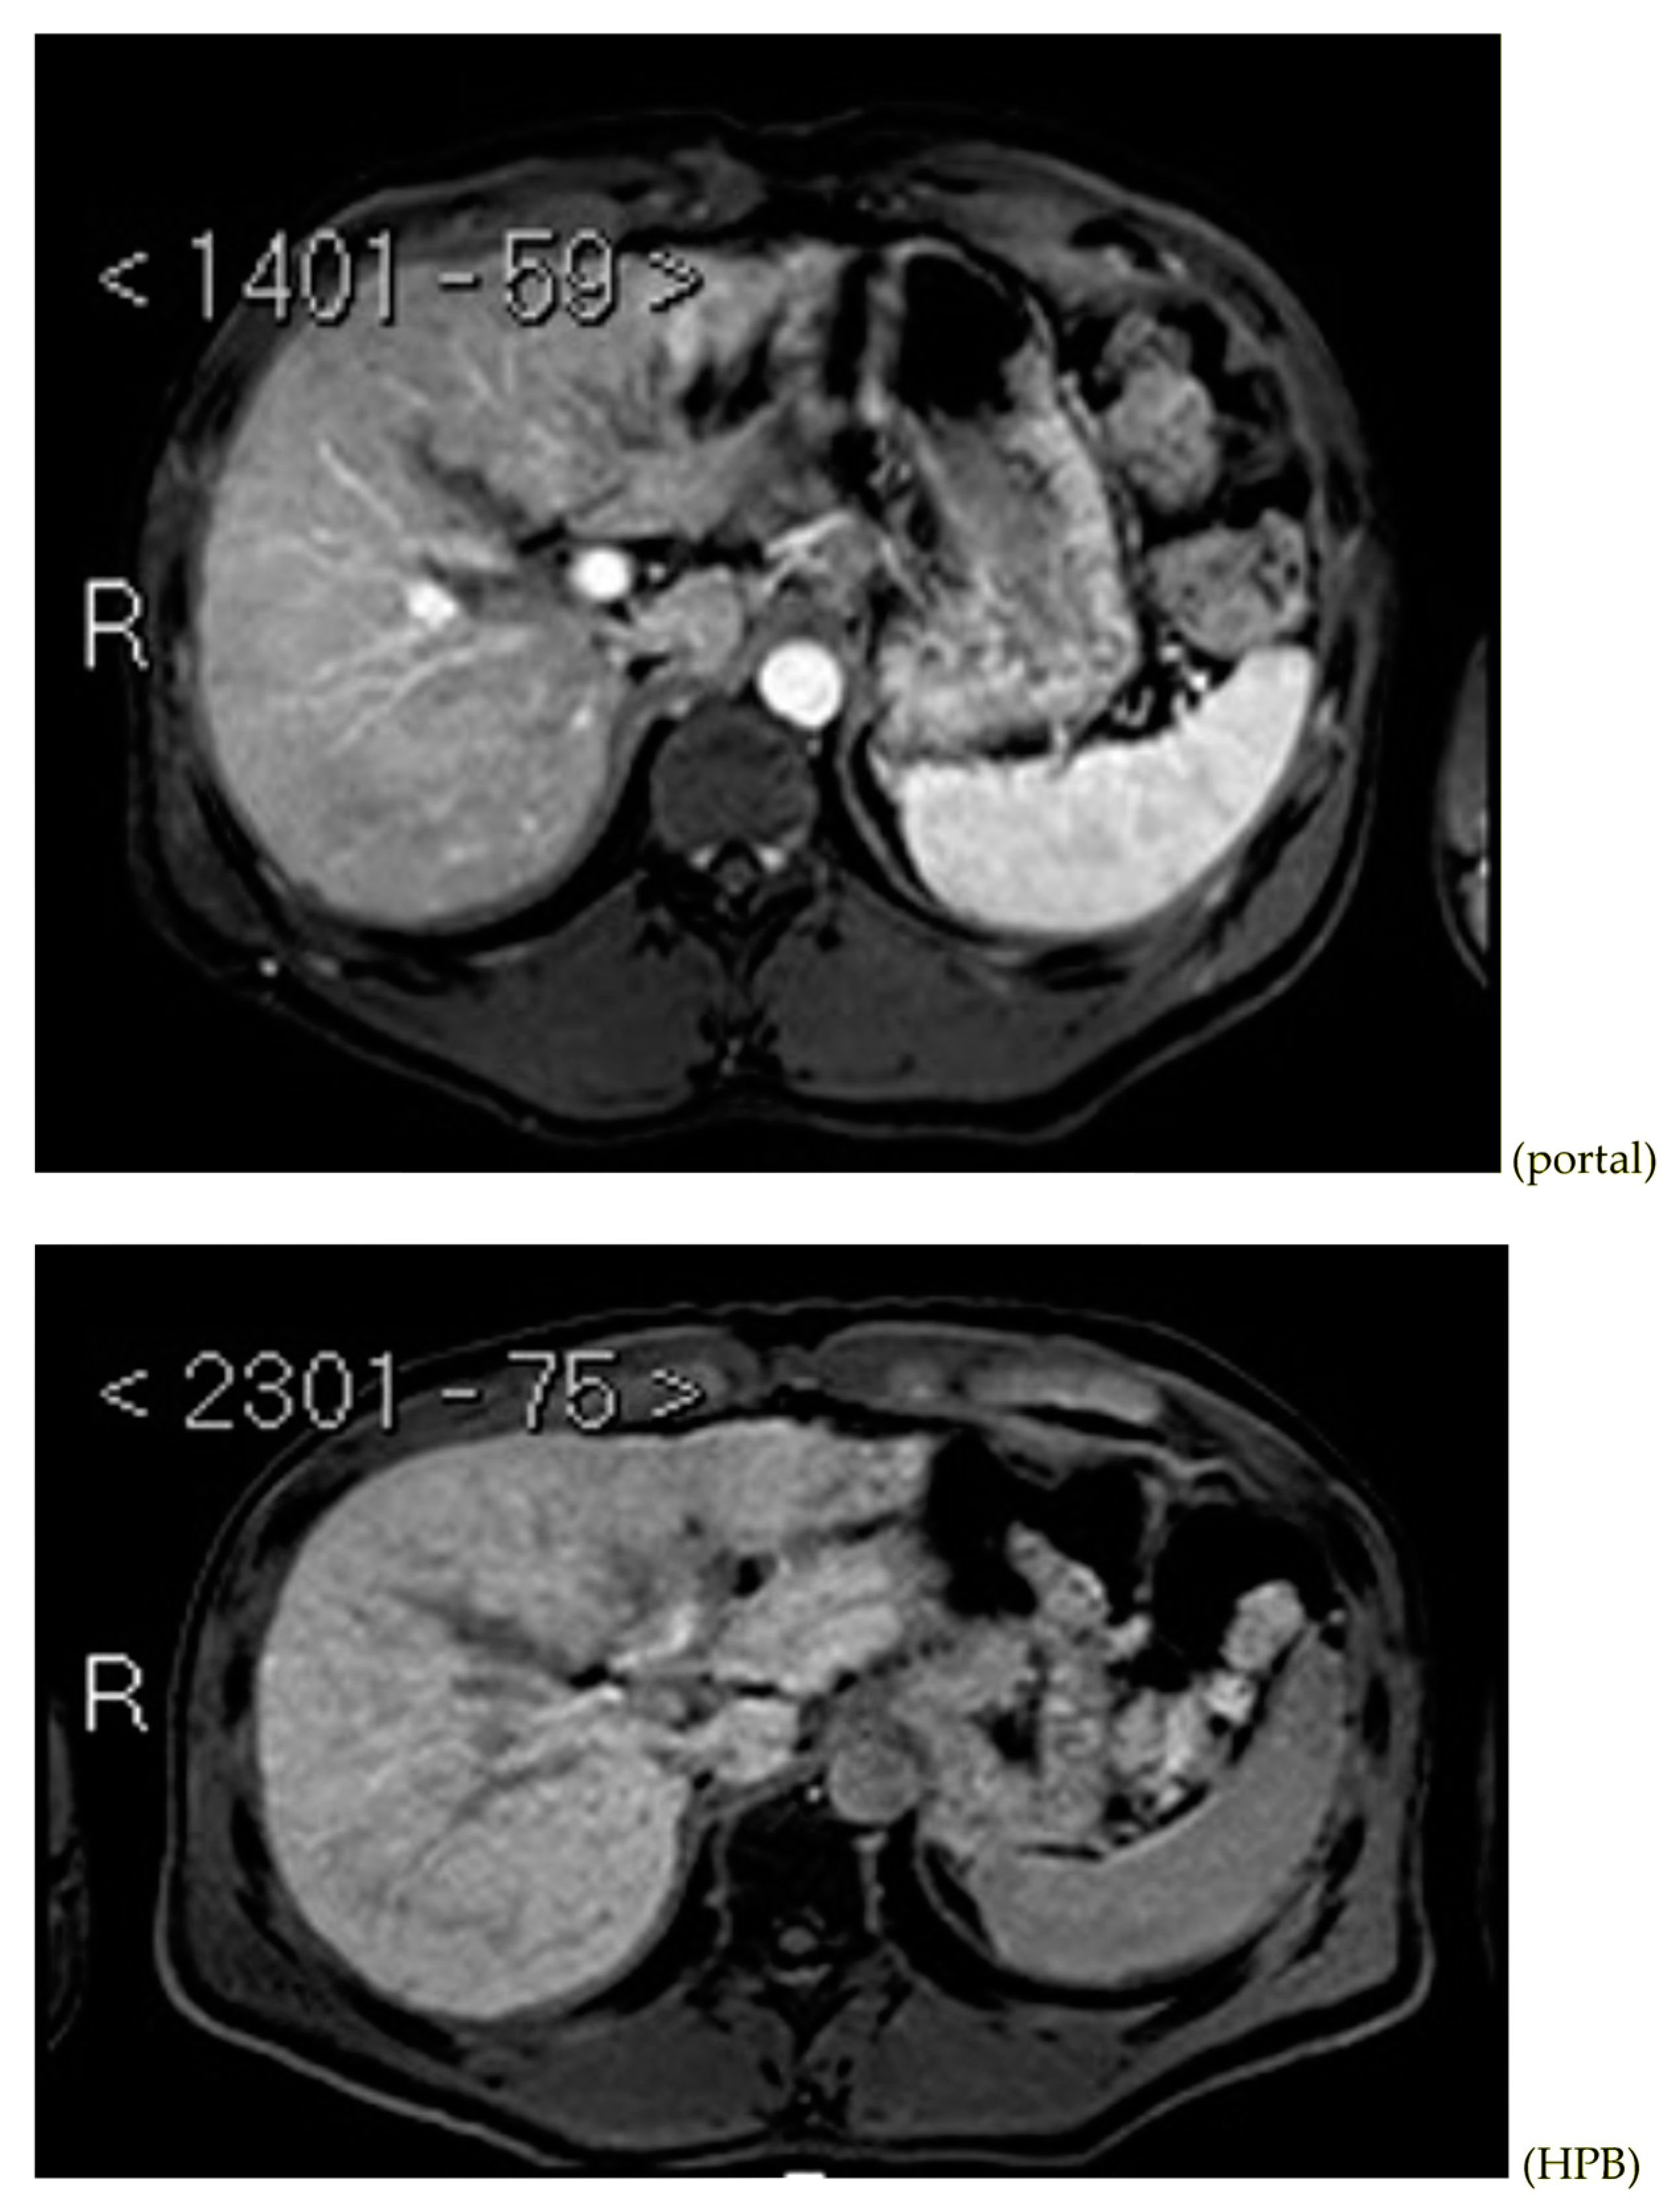

Subsequently, an upper-abdomen Computed Tomography (CT) scan and liver Magnetic Resonance Imaging (MRI) were performed (Figure 1, Figure 2, Figure 3, Figure 4, Figure 5, Figure 6 and Figure 7).

Figure 2.

CT portal phase.

MRI T1, T1 in, T1 out, and DWI.

MRI arterial, portal, and HPB phases.

A mass of 1.8 cm was detected within the biliary branch for the third hepatic segment, characterized by nodular impregnation in the arterial phase and irregular and partial washout in the portal venous phase. These findings were compatible with a heterologous lesion, although it was not possible to perform a diagnosis among HCC, intrahepatic CCA or other pathological lesions.

HCC typically has an increased arterial blood supply, so it usually shows hyperattenuation in the arterial phase and hypoattenuation in the portal venous phase, compared to the hepatic parenchyma.

Most HBDTTs should show the same enhancement pattern. However, some HCCs can show iso- or hypoattenuation in the arterial phase, with the enhancement in the arterial phase inversely correlated with the degree of blood clots and necrosis. So, hypoattenuation in the portal venous phase seems to be the most important imaging feature to distinguish HCC with BDTT from perihilar CCA [17].

Washout in the portal venous phase is also the main feature to distinguish HCC with BDTT from intrahepatic CCA, together with the presence of tortuous tumoral vessels [17].